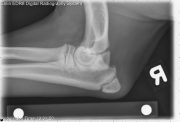

Today’s case is a 5 month old male Labrador Retriever with one week history of left thoracic limb lameness. What is the cause of the lameness?

L LAT Elbow

• Left elbow: There is a smoothly margined osseous body medial to the medial epicondyle of the humerus. There is a radiolucent region in the medial epicondyle at this site.

• Right elbow: There is a radiolucent region in the medial epicondyle, and the subchondral bone in this region is sclerotic.

Ununited medial epicondyle or flexor tendon enthesopathy of the left elbow. Probable smaller lesion of the right elbow.

A CT examination of the elbows was performed. There was a completely separate fragment on the left medial epicondyle, and a fissure and subchondral bone sclerosis of the right medial epicondyle. Previously named ununited medial epicondyle, new terminology of flexor tendon enthesopathy has been proposed for this condition.